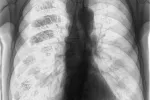

Si no es diagnosticada a tiempo, es posible que la tuberculosis deje algunas secuelas en el pulmón3, como pequeñas cicatrices, lo que no implica que el tratamiento sea menos efectivo; es decir, que la infección es igualmente erradicada. Sin embargo, el pulmón puede no funcionar tan bien como antes de sufrir la tuberculosis. Por ello, muchas veces el médico solicita una espirometría al final del tratamiento para comprobar el funcionamiento del pulmón una vez que ha sido curada la tuberculosis.